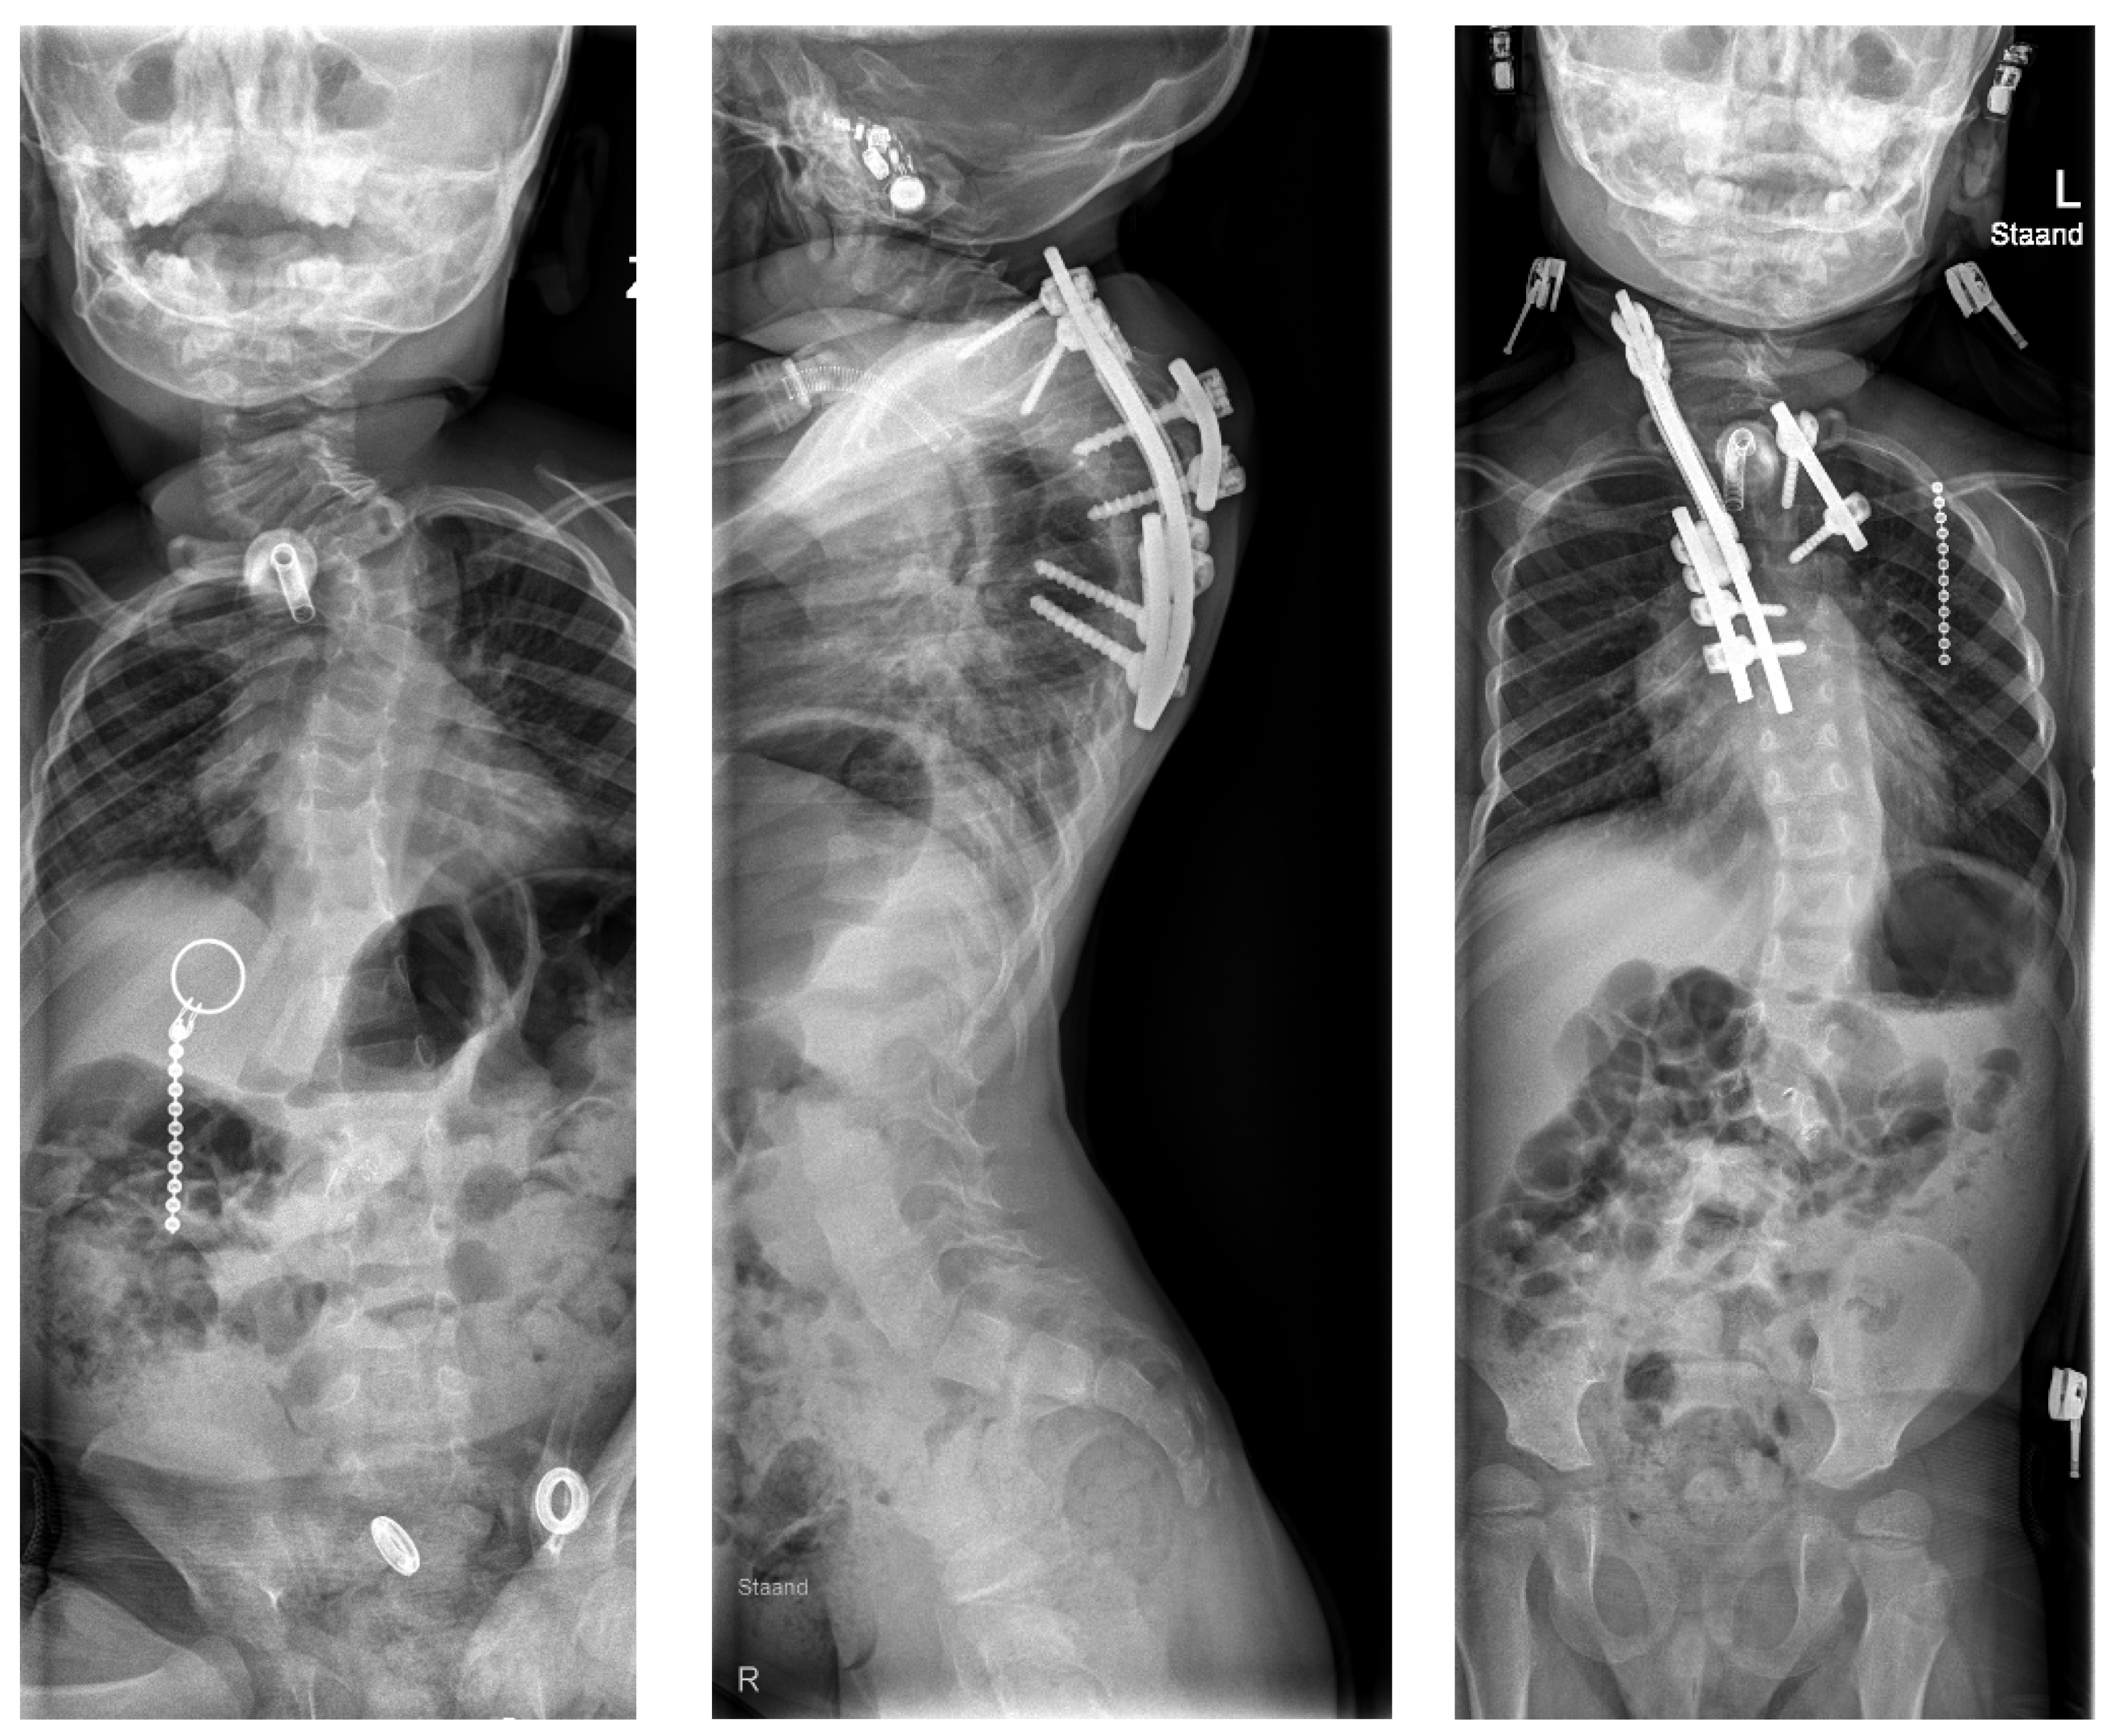

5. Pathway 2: Spinal Column Prosthesis

Background

6.3. Clinical Experience with Spinal Prosthesis